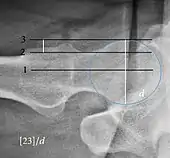

| Crossing ratio | ![]() |

Percentage of acetabular walls crossing. Normal acetabulum is oriented in anteversion. Its value ranges from 15 to 20° in the equatorial plane of the acetabulum and decreases gradually towards the acetabular roof, where normal values range from 0 to 5°. Retroversion of the upper part of the acetabulum has been related with pincer type impingement. In radiography the presence of a "crossover sign" is produced when the posterior wall of the acetabulum crosses the anterior wall before reaching the acetabular roof. It is a sign of acetabular retroversion and it has been linked with overcoverage and pincer impingement. Nevertheless, this sign has been described in 6% of the normal population. Therefore, more important than its presence is the percentage of crossing. | <20%

|